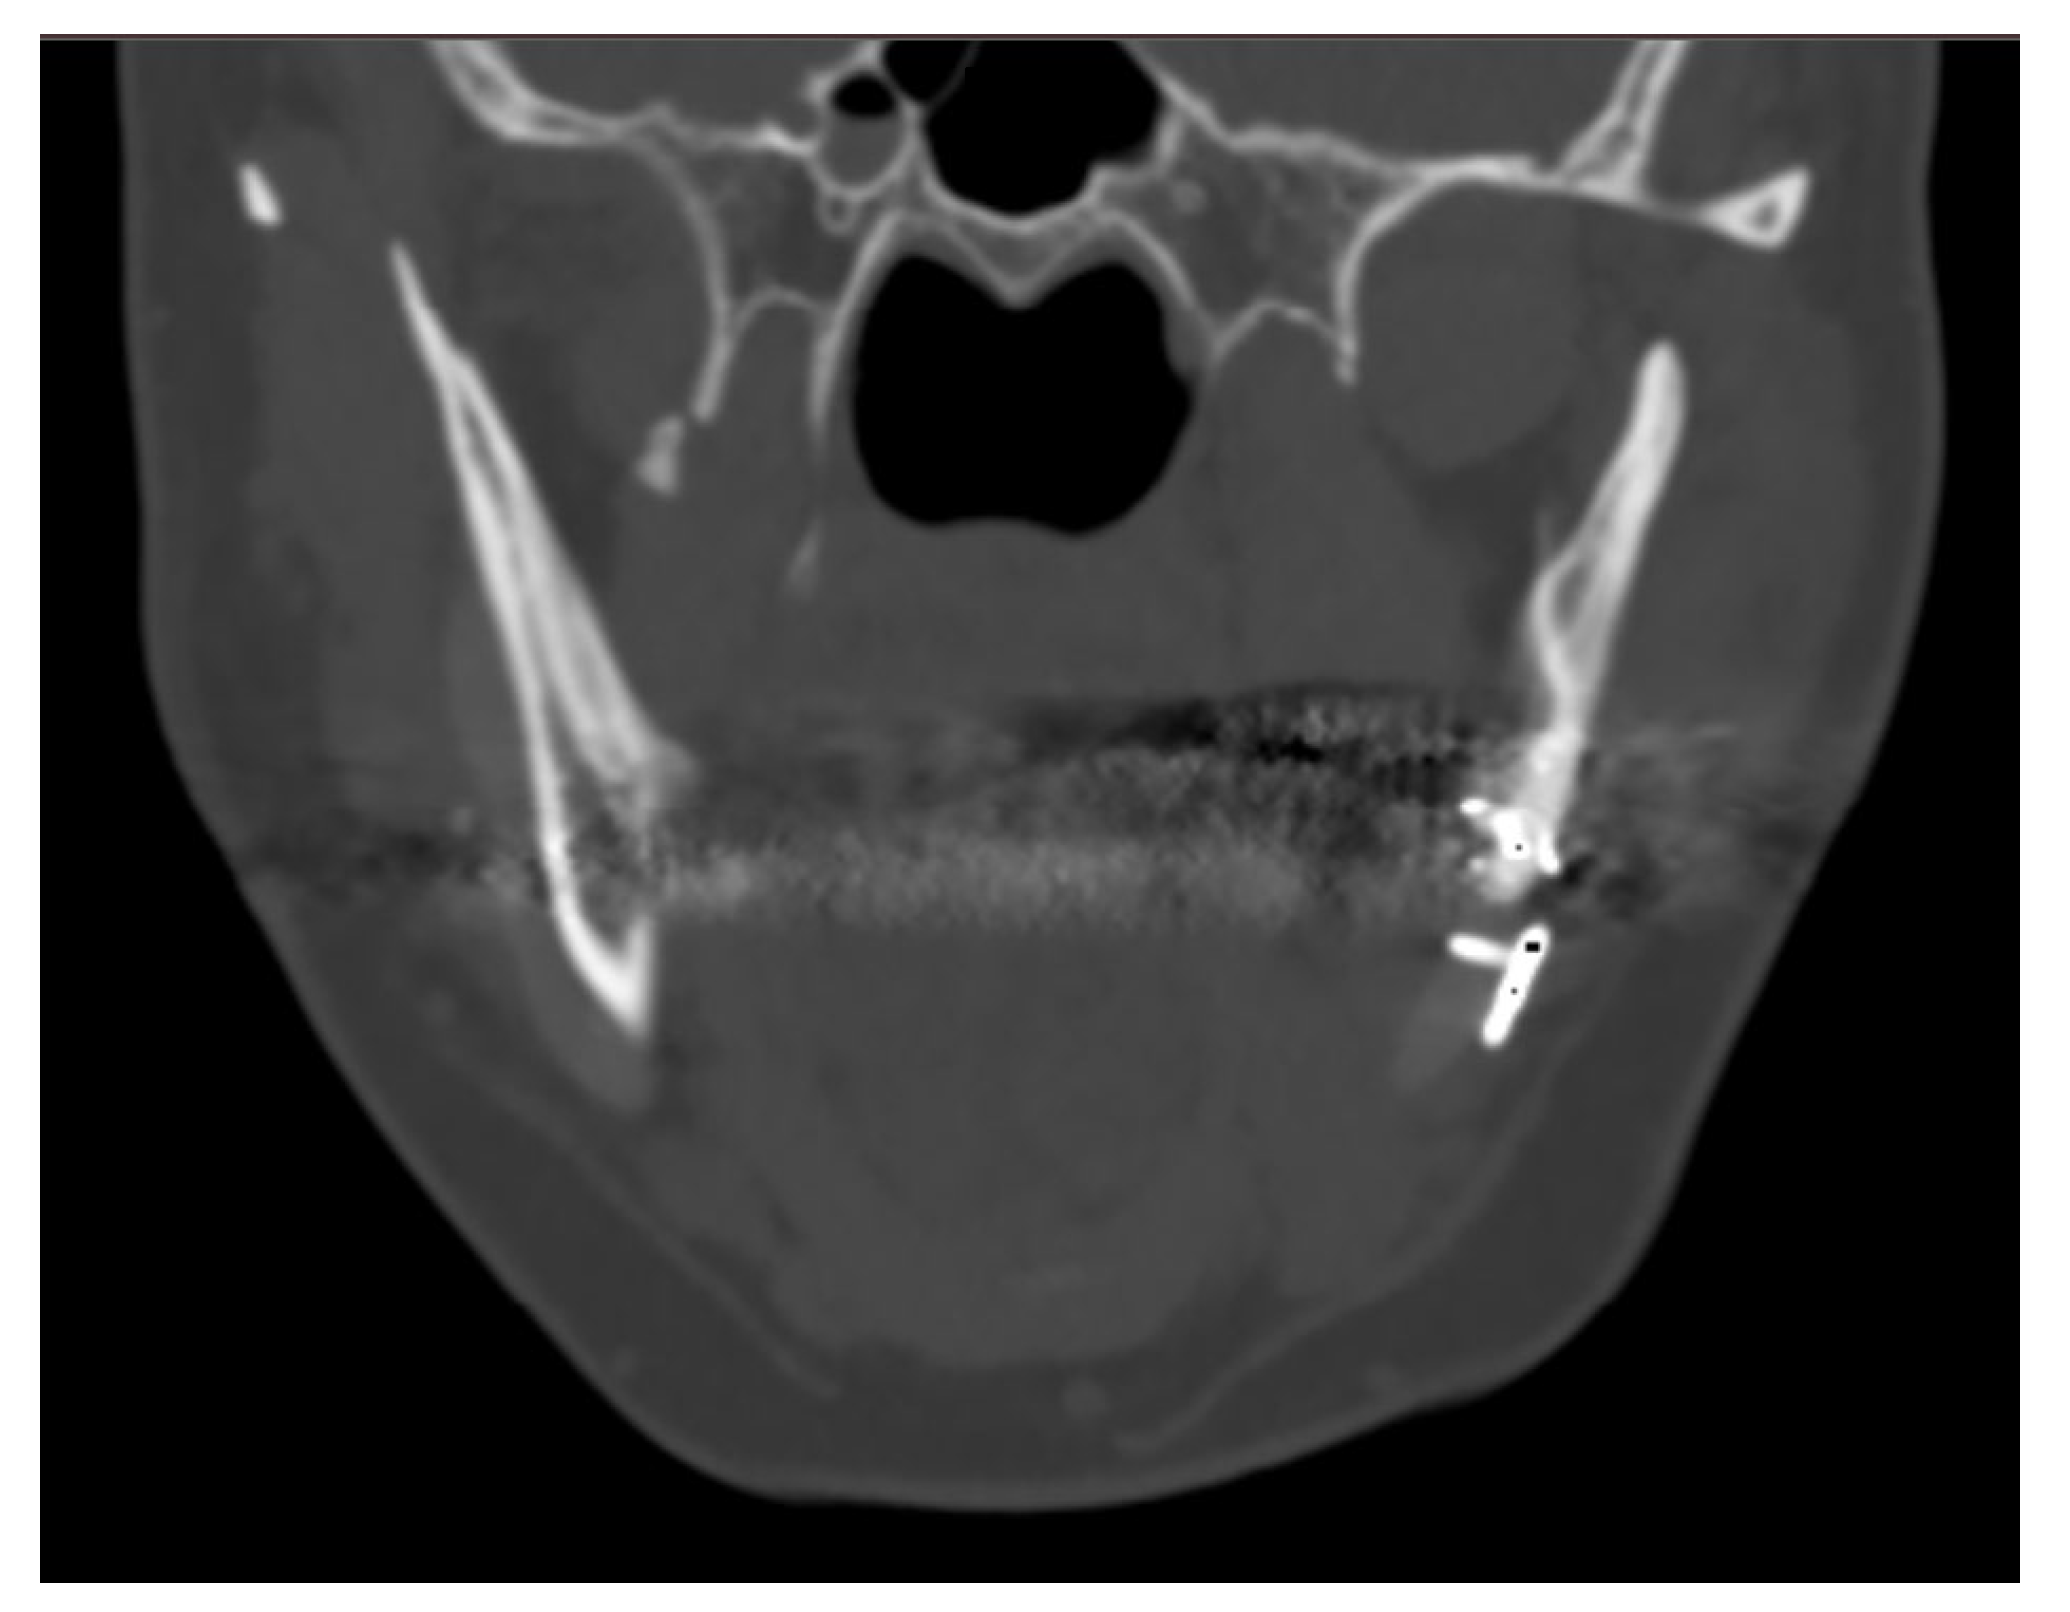

The case of neurosurgery underscores the potential of PEEK prosthetic implants to cause bone resorption in surrounding tissue (see Figure 2). In this instance, the observed bone resorption was minimal and did not require further intervention. Factors influencing this phenomenon include not only the material but also the design, mechanical loading, and notably, the interface between the implant and the periosteum. Titanium implants, while studies comparing different materials for craniofacial reconstruction are still limited, appear to be associated with increased donor site comorbidity, including bone resorption [39]. Countless studies have demonstrated that implants crafted from specific materials, such as titanium alloys, may induce peri-implant bone resorption attributable to stress shielding phenomena [40,41]. Stress shielding is a biomechanical phenomenon that leads to adaptive changes in bone strength due to the altered distribution of physiological loads on the bone, potentially leading to implant loosening. The elastic modulus of PEEK is comparable to those of cortical bone, so it exhibits less stress shielding than the Ti material [42]. Modifying PEEK through the addition of other materials, such as carbon fibers, is one of the techniques aimed at improving these effects, as observed in our case [43,44]. As mentioned previously, mechanical loading also plays a crucial role in potential bone resorption. Several studies have demonstrated that the mechanical behavior of implants under impact loading depends on the mechanical characterization of individual human tissues and regions [45]. This can influence the observation of bone resorption, as seen in our neurosurgical case. Finally, the micromotion of the implant, particularly observed in dental implants, could play a role in bone resorption and help explain the case observed in neurosurgery. Therefore, careful consideration of these factors is crucial in mitigating bone resorption and ensuring the long-term stability of prosthetic implants.

Figure 2.

The neurosurgery case representing bone resorption. (a): Lateral 3D view, loaded with low volume rendering; (b) lateral 3D view, loaded with high volume rendering focusing on the PEEK prothesis and bone resorption underneath the prosthesis.